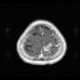

Carcinomatous infiltration

Leptomeningeal cancer (also called leptomeningeal carcinomatosis, leptomeningeal disease (LMD), leptomeningeal metastasis, neoplastic meningitis, meningeal metastasis and meningeal carcinomatosis) is a rare complication of cancer in which the disease spreads from the original tumor site to the meninges surrounding the brain and spinal cord. This leads to an inflammatory response, hence the alternative names neoplastic meningitis (NM), malignant meningitis, or carcinomatous meningitis. [Source: Wikipedia ]